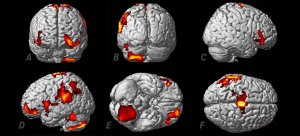

Aquí se ven las regiones del cerebro significativamente activadas mientras el participante estaba teniendo experiencias extracorpóreas.

Las regiones activadas más significativamente están lateralizadas hacia el lado izquierdo e incluyen el área motora suplementaria (F), el cerebelo (B, D, E), la circunvolución supramarginal (D, F), la circunvolución temporal inferior (B, D, F), las circunvoluciones orbitofrontales media y superior (A, C, D, E).